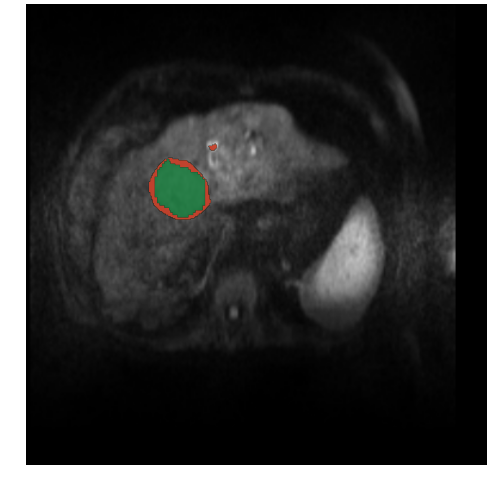

3.3.3 Qualitative and Quantitative Results

As seen in figure 8, the CFCN was able to segment the liver lesion correctly. In both cases the CFCN undersegments the lesion leading to a Dice score of 85% in both cases. The quantitative segmentation results are shown in table 1. The Cascaded U-Net was able to reach a dice score for liver in MR-DWI of 87%. For lesion we found a mean dice score of 69.7%.

Refer to caption

Figure 8: Automatic lesion segmentation with cascaded fully convolutional neural networks (CFCN) in DW-MRI. The raw DW-MRI slices (left), were automatically segmented with our proposed method. Green depicts correctly segmented lesion pixels. Red shows false positive and false negative, i.e. all wrong predictions, of the lesions. In both cases the proposed CFCN achieves an dice score for lesions of 85%.